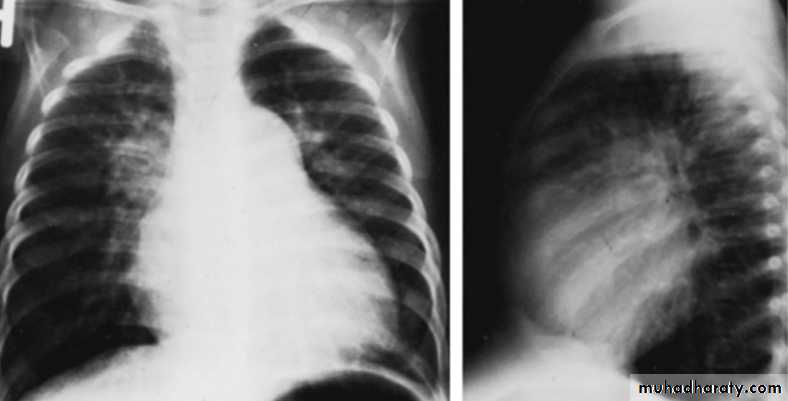

With large VSD cardiomegaly of varying degrees is present and involves the LA, left ventricle (LV), and sometimes RV. Pulmonary vascular markings increase. The degree of cardiomegaly and the increase in pulmonary vascular markings directly relate to the magnitude of the Lt to Rt shunt.CXR of 6 years old child PA and lateral views showing cardiac enlargement and increased pulmonary markings

CXR of 6 years old child PA and lateral views showing cardiac enlargement and increased pulmonary markings